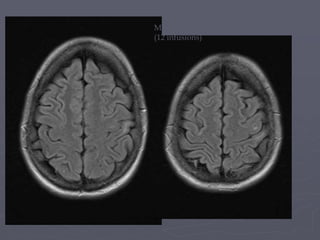

March 23rd 2011

(12 infusions)

26th May 2011 (14 infusions)